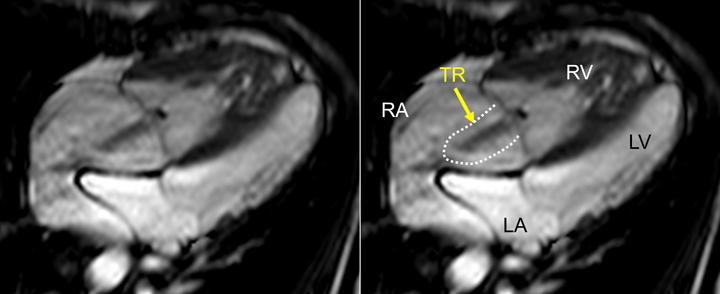

1. a)詳細な解析を行う前に,すべてのシネ画像を確認し全体像を把握する.また同時に,各断面の観察を行い,アーチファクトの有無をチェックする.CMRは心電図同期下に撮影・作像するため,特に不整脈患者でアーチファクトを来しやすい.重度の不整脈患者では,収縮末期容積が過大評価され,駆出率が過小評価される傾向がある.シネMRI画像で弁逆流の定量的評価はできないが,血流を描出できるため,逆流の定性的な評価は可能であり,最初に確認しておく(Fig. 7).ただし,同一平面上の逆流しか描けないため,同一平面上に吹かない逆流については逆流の程度をunder estimateしてしまうことにも注意が必要である.

Pediatric Cardiology and Cardiac Surgery 40(4): 260-271 (2024)

Fig. 7 4 chamber view. Thick black line surrounded by dashed lines is tricuspid regurgitation (yellow arrow)

LA, left atrium; LV, left ventricle; RA, right atrium; RV, right ventricle; TR, tricuspid regurgitation